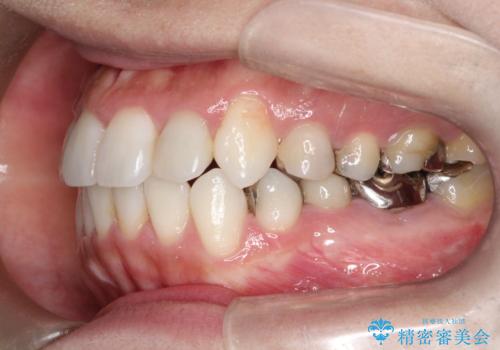

インビザラインで目立たない矯正 ガタガタの歯並びをきれいな歯並びへ

- 全体的なガタガタが気になるとのことで来院されました。

歯と歯のあいだをわずかに削りスペースを作り、ガタガタを改善する計画としました。

装着時間をしっかり守っていただけたのでスムーズに治療をすすめることができました。